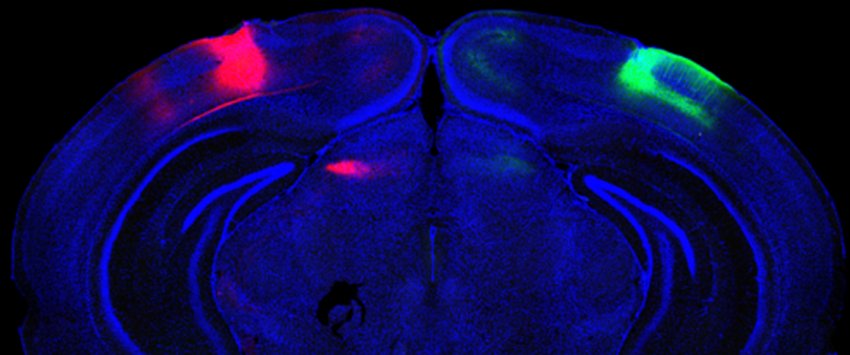

Scienziati hanno tracciato e studiato i neuroni che collegano le cortecce visive in entrambi gli emisferi del cervello. (Fonte: MIT)

Nello studio, Adaikkan, Tsai, Thomas McHugh e i coautori hanno scoperto e tracciato i neuroni V1 che estendevano i loro assoni attraverso il [[corpo calloso]], che collega gli emisferi del cervello, con le cellule V1 sull'altro lato del cervello.

Lì, hanno scoperto, i neuroni inter-emisferici (CH, cross-hemispheric) forgiavano connessioni o sinapsi, con cellule puntate, fornendo loro una stimolazione 'eccitatoria' per guidare la loro attività. Adaikkan ha anche scoperto che i neuroni CH avevano molte più probabilità di essere attivati da un compito di discriminazione della novità rispetto ai neuroni V1 in generale o dei neuroni in altre regioni fortemente coinvolte nella memoria come l'ippocampo o la corteccia prefrontale.